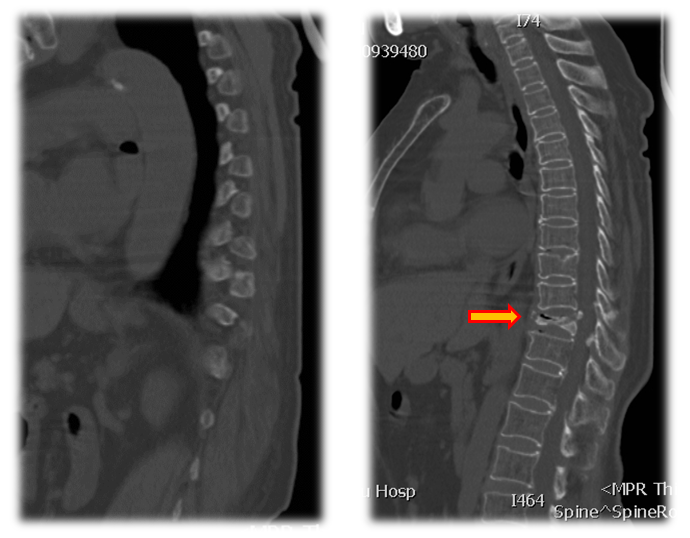

术前CT

术前MRI

术前诊断:1.胸腰椎后凸畸形,2.重度骨质疏松症,3.Kummell病II期,4.胸椎椎管狭窄,5.黄韧带骨化症,6.高血压病。

手术治疗:T10-T12棘突椎板切除;T11 截骨后凸矫形;T9-L1椎弓根固定,均为骨水泥螺钉,安放横联两根;T10/11及各椎板后方大量植异体骨及自体骨。

术中透视

术后X线

术后CT